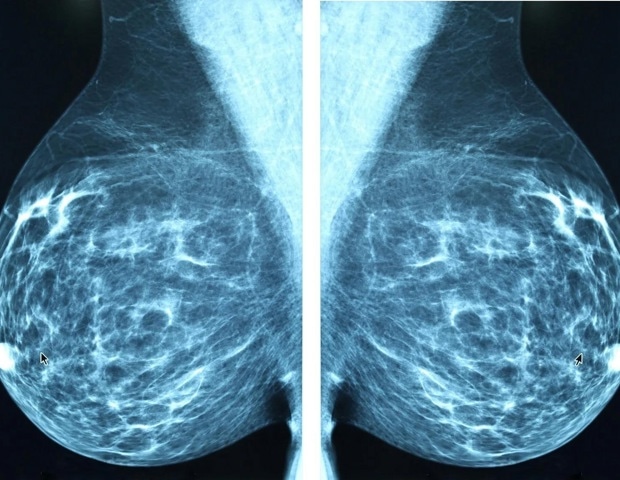

МРТ молочной железы обычно включается в диагностическое обследование рака молочной железы из-за ее способности выявлять заболевание, которое не может быть обнаружено с помощью маммографии, - объяснила Изабель Бедросян, доктор медицинских наук, ведущий исследователь исследования, хирург-онколог и профессор хирургической онкологии молочной железы в Онкологическом центре МД Андерсона Техасского университета.

Все пациенты прошли диагностическую маммографию с ультразвуком или без него до включения в исследование, пациенты были случайным образом распределены для прохождения дополнительных исследований. визуализация с помощью МРТ молочной железы (группа МРТ) или отсутствие дальнейшей визуализации (группа без МРТ). Доля женщин, перенесших лампэктомию и получивших адъювантное облучение, была одинаковой в обеих группах.